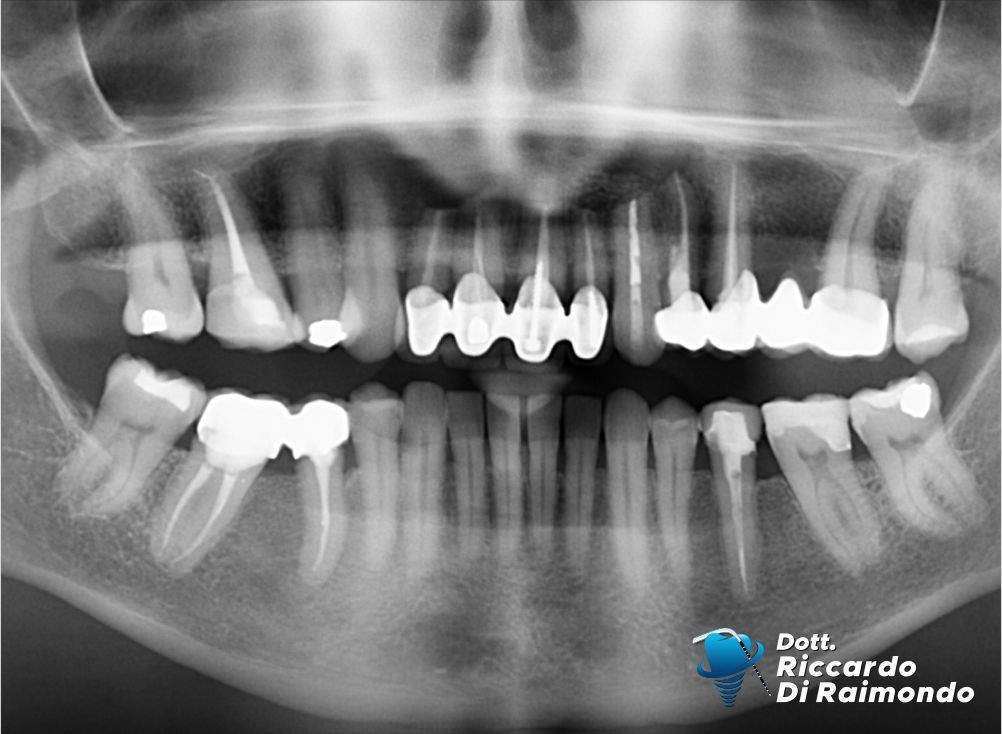

Rimozione cisti mascellare superiore frontale

Prima del Trattamento